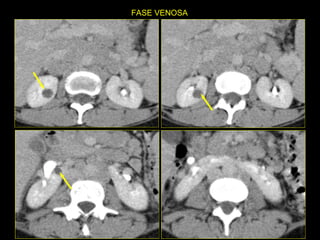

Caso # 4 ♀ , 5ta década de la vida  Presenta dolor abdominal difuso sin poder determinarse la causa clínicamente por lo que se solicita la TC Estudio con cortes axiales y coronales demostrándose  fases arterial y venosa.

Hallazgos Caso #4: Riñón en herradura. Área cuneiforme de disminución de la atenuación en el istmo del riñón en herradura en relación con proceso inflamatorio focal que es exquisitamente demostrada en las RMP coronales.  Lesiones hipodensas, redondeadas en riñón derecho, las cuales no muestran aumento en el valor de atenuación con la ministración del medio de contraste en relación con quistes Bosniak I.